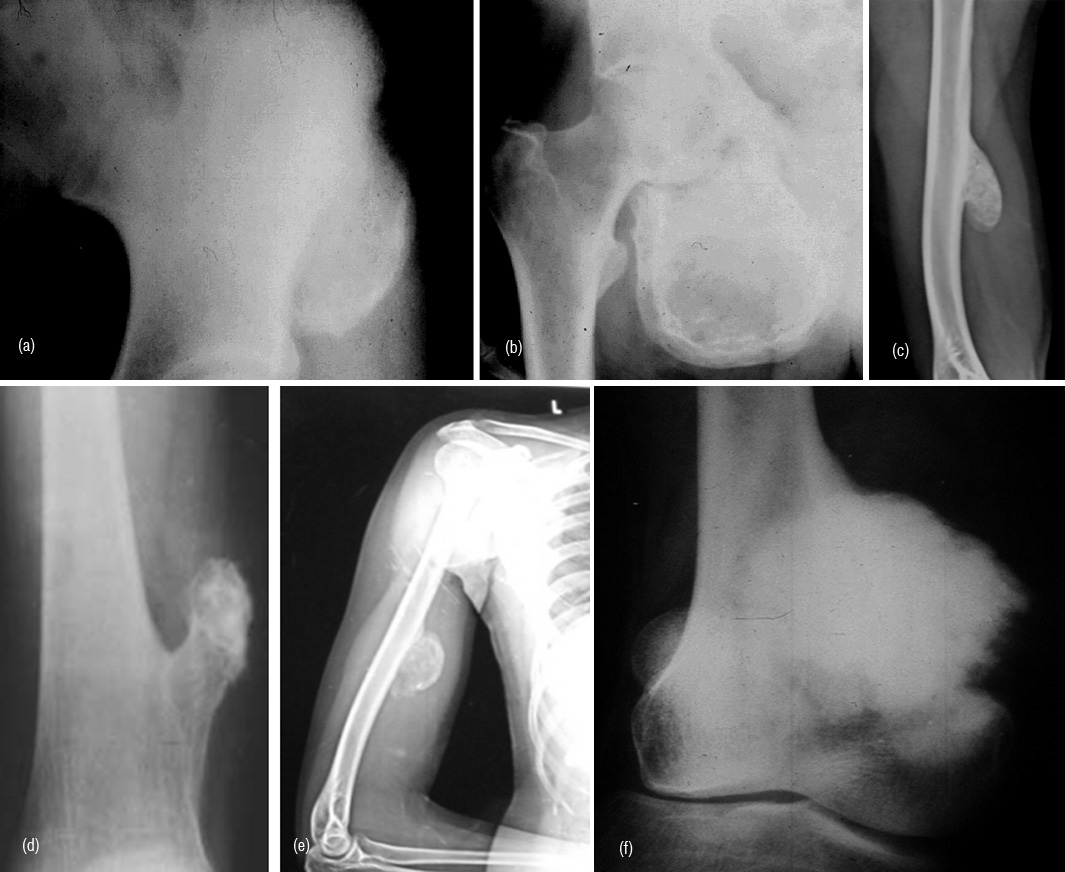

Post traumatic bone lesion

In avulsive lesions of apophysis, the healing phase of the lesion simulates a bone tumor such as pariosteal osteosarcoma (Figure 9ab). This is due to abundant callus and associated calcified hematoma with myositis ossificans. These lesions are well circumscribed without any soft tissue swelling. If one is not familiar with this entity, these may be mistaken for benign or malignant osteogenic tumors. Post traumatic myositis ossificans can occasionally simulate osteochondroma or other benign bone lesion (Figure 9cde). In a bedridden patient due to neurological cause’s dystrophic calcification/ ossification is commonly encountered in the soft tissues particularly in pelvic region which may be mistaken for an osseous tumor such as pariosteal osteosarcoma (Figure 9f).

Figure 9: (a) Avulsion injury at the attachment of rectus femoris to anterior inferior iliac spine, (b) Avulsion injury of the adductors to ischial apophysis. Note the abundant callus and myositis ossificans. (c) Post traumatic myositis ossificans, (d) Exostosis, (e) Myositis ossificans, (f) Pariosteal osteosarcoma.